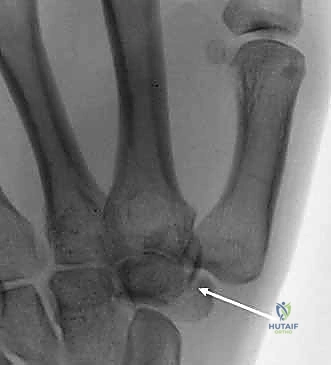

- العظم الكلابي (Hamate): يمتلك بروزاً عظمياً يُسمى "الخطاف". كسور هذا الخطاف شائعة بين الرياضيين (لاعبي التنس، الجولف، البيسبول) وتسبب ألماً مزمناً إذا لم تُشخص.

شاب رياضي (25 عاماً) سقط أثناء ممارسة كرة السلة وعانى من ألم مزمن في قاعدة اليد لمدة 3 أشهر، تم تشخيصه خطأً على أنه التواء. بعد زيارته لعيادة الدكتور هطيف، أظهرت الأشعة المقطعية الدقيقة كسراً في "خطاف العظم الكلابي" (Hamate hook fracture). تم إجراء عملية جراحية دقيقة لاستئصال الجزء المكسور الصغير الذي كان يضغط على الأوتار. بعد 6 أسابيع من التأهيل، عاد اللاعب لممارسة الرياضة بكامل كفاءته.